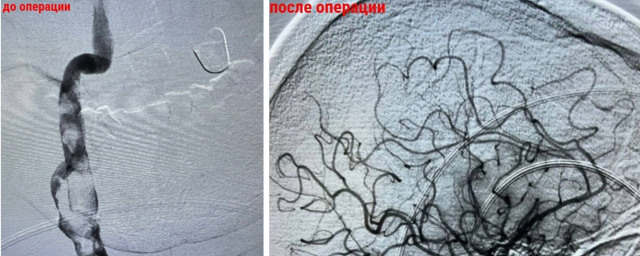

Врачи под рентген-контролем провели тромбэкстракцию: сделали небольшой прокол в бедре и ввели специальный катетер к сосудам головного мозга, благодаря чему смогли удалить тромб. Операция заняла 45 минут. Мужчина уже выписался на амбулаторное лечение. Он продолжит принимать антикоагулянты.